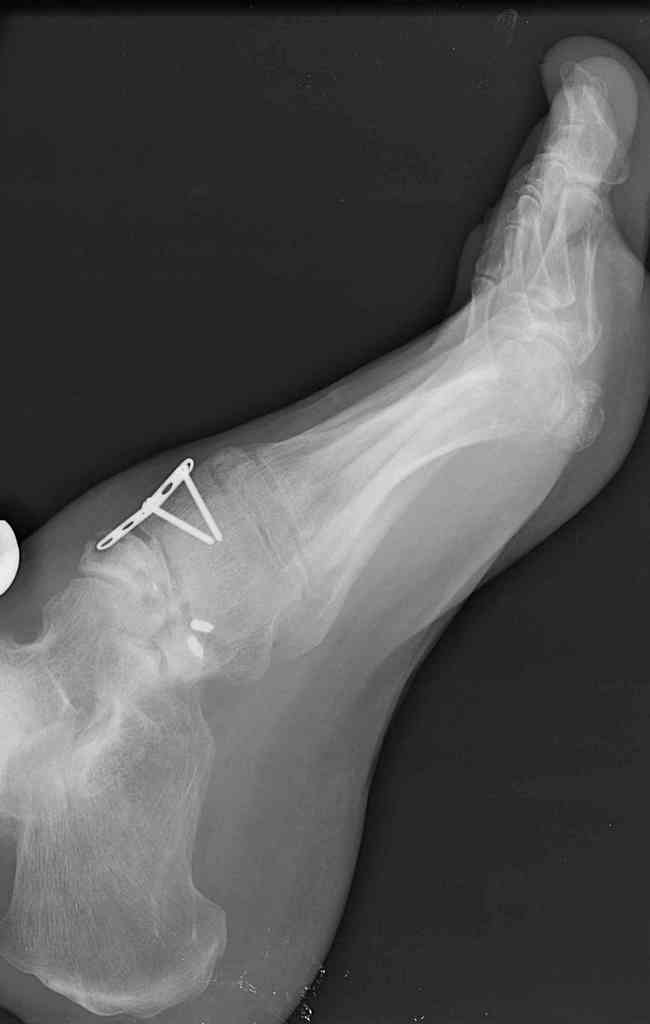

This is a 44 year old male laborer, smoker, who had his foot caught in a forklift about a year ago.

He had an ORIF and subsequent removal of hardware and presented to me with severe midfoot pain. His medial column is grossly unstable on exam but is passively correctable. Wounds are well healed, no sign of infection.

I haven't found much literature on salvage for this. What next? Iliac crest graft for structure with talo-navicular-cuneiform arthrodesis to restore the medial column? Will this fuse as an isolated procedure and given the loss of most of his subtalar motion, would a talocalcaneal arthrodesis improve his chances of fusion?